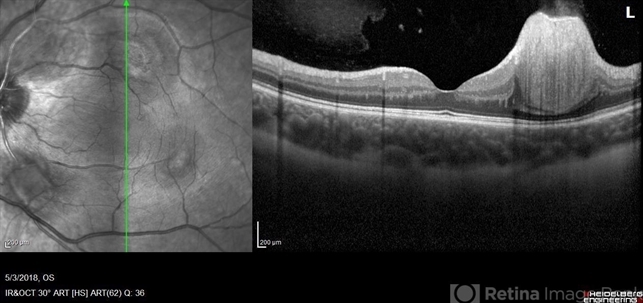

- astrocytic hamartoma, optical coherence tomography (OCT), Heidelburg Spectralis, left eye, infrared image, tuberous sclerosis

Optical coherence tomography system

Heidelberg Spectralis - Description

- Optical coherence tomography of a 7-year-old female with multiple astrocytic harmartomas as a retinal manifestation of tuberous sclerosis. Patient came to our office to rule out possible drug toxicity from Sabril, a an anticonvulsant. There were no signs of retinal toxicity by extended ophthalmoscopy or imaging, yet she will be monitored every 6 months.